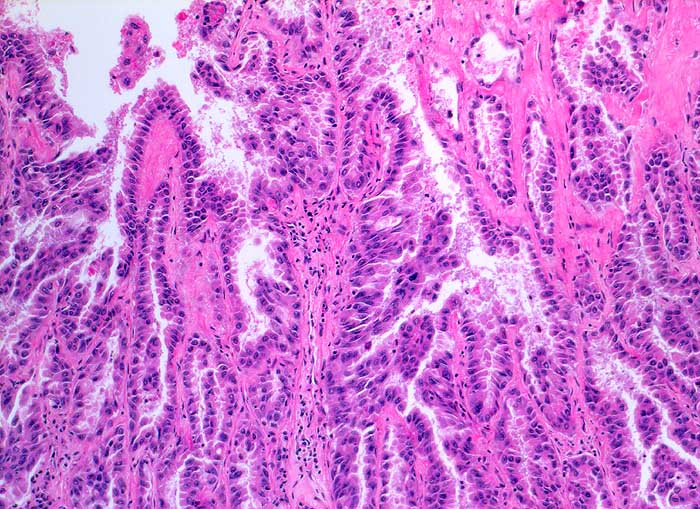

PathoPic ID 5812 - Adenokarzinom der Lunge

Adenokarzinom der Lunge

maligner Tumor

Lunge

Papilläre und tubuläre Strukturen ausgekleidet von atypischem hochprismatischem Epithel entsprechend einem hochdifferenzierten Adenokarzinom.

Histologie

100